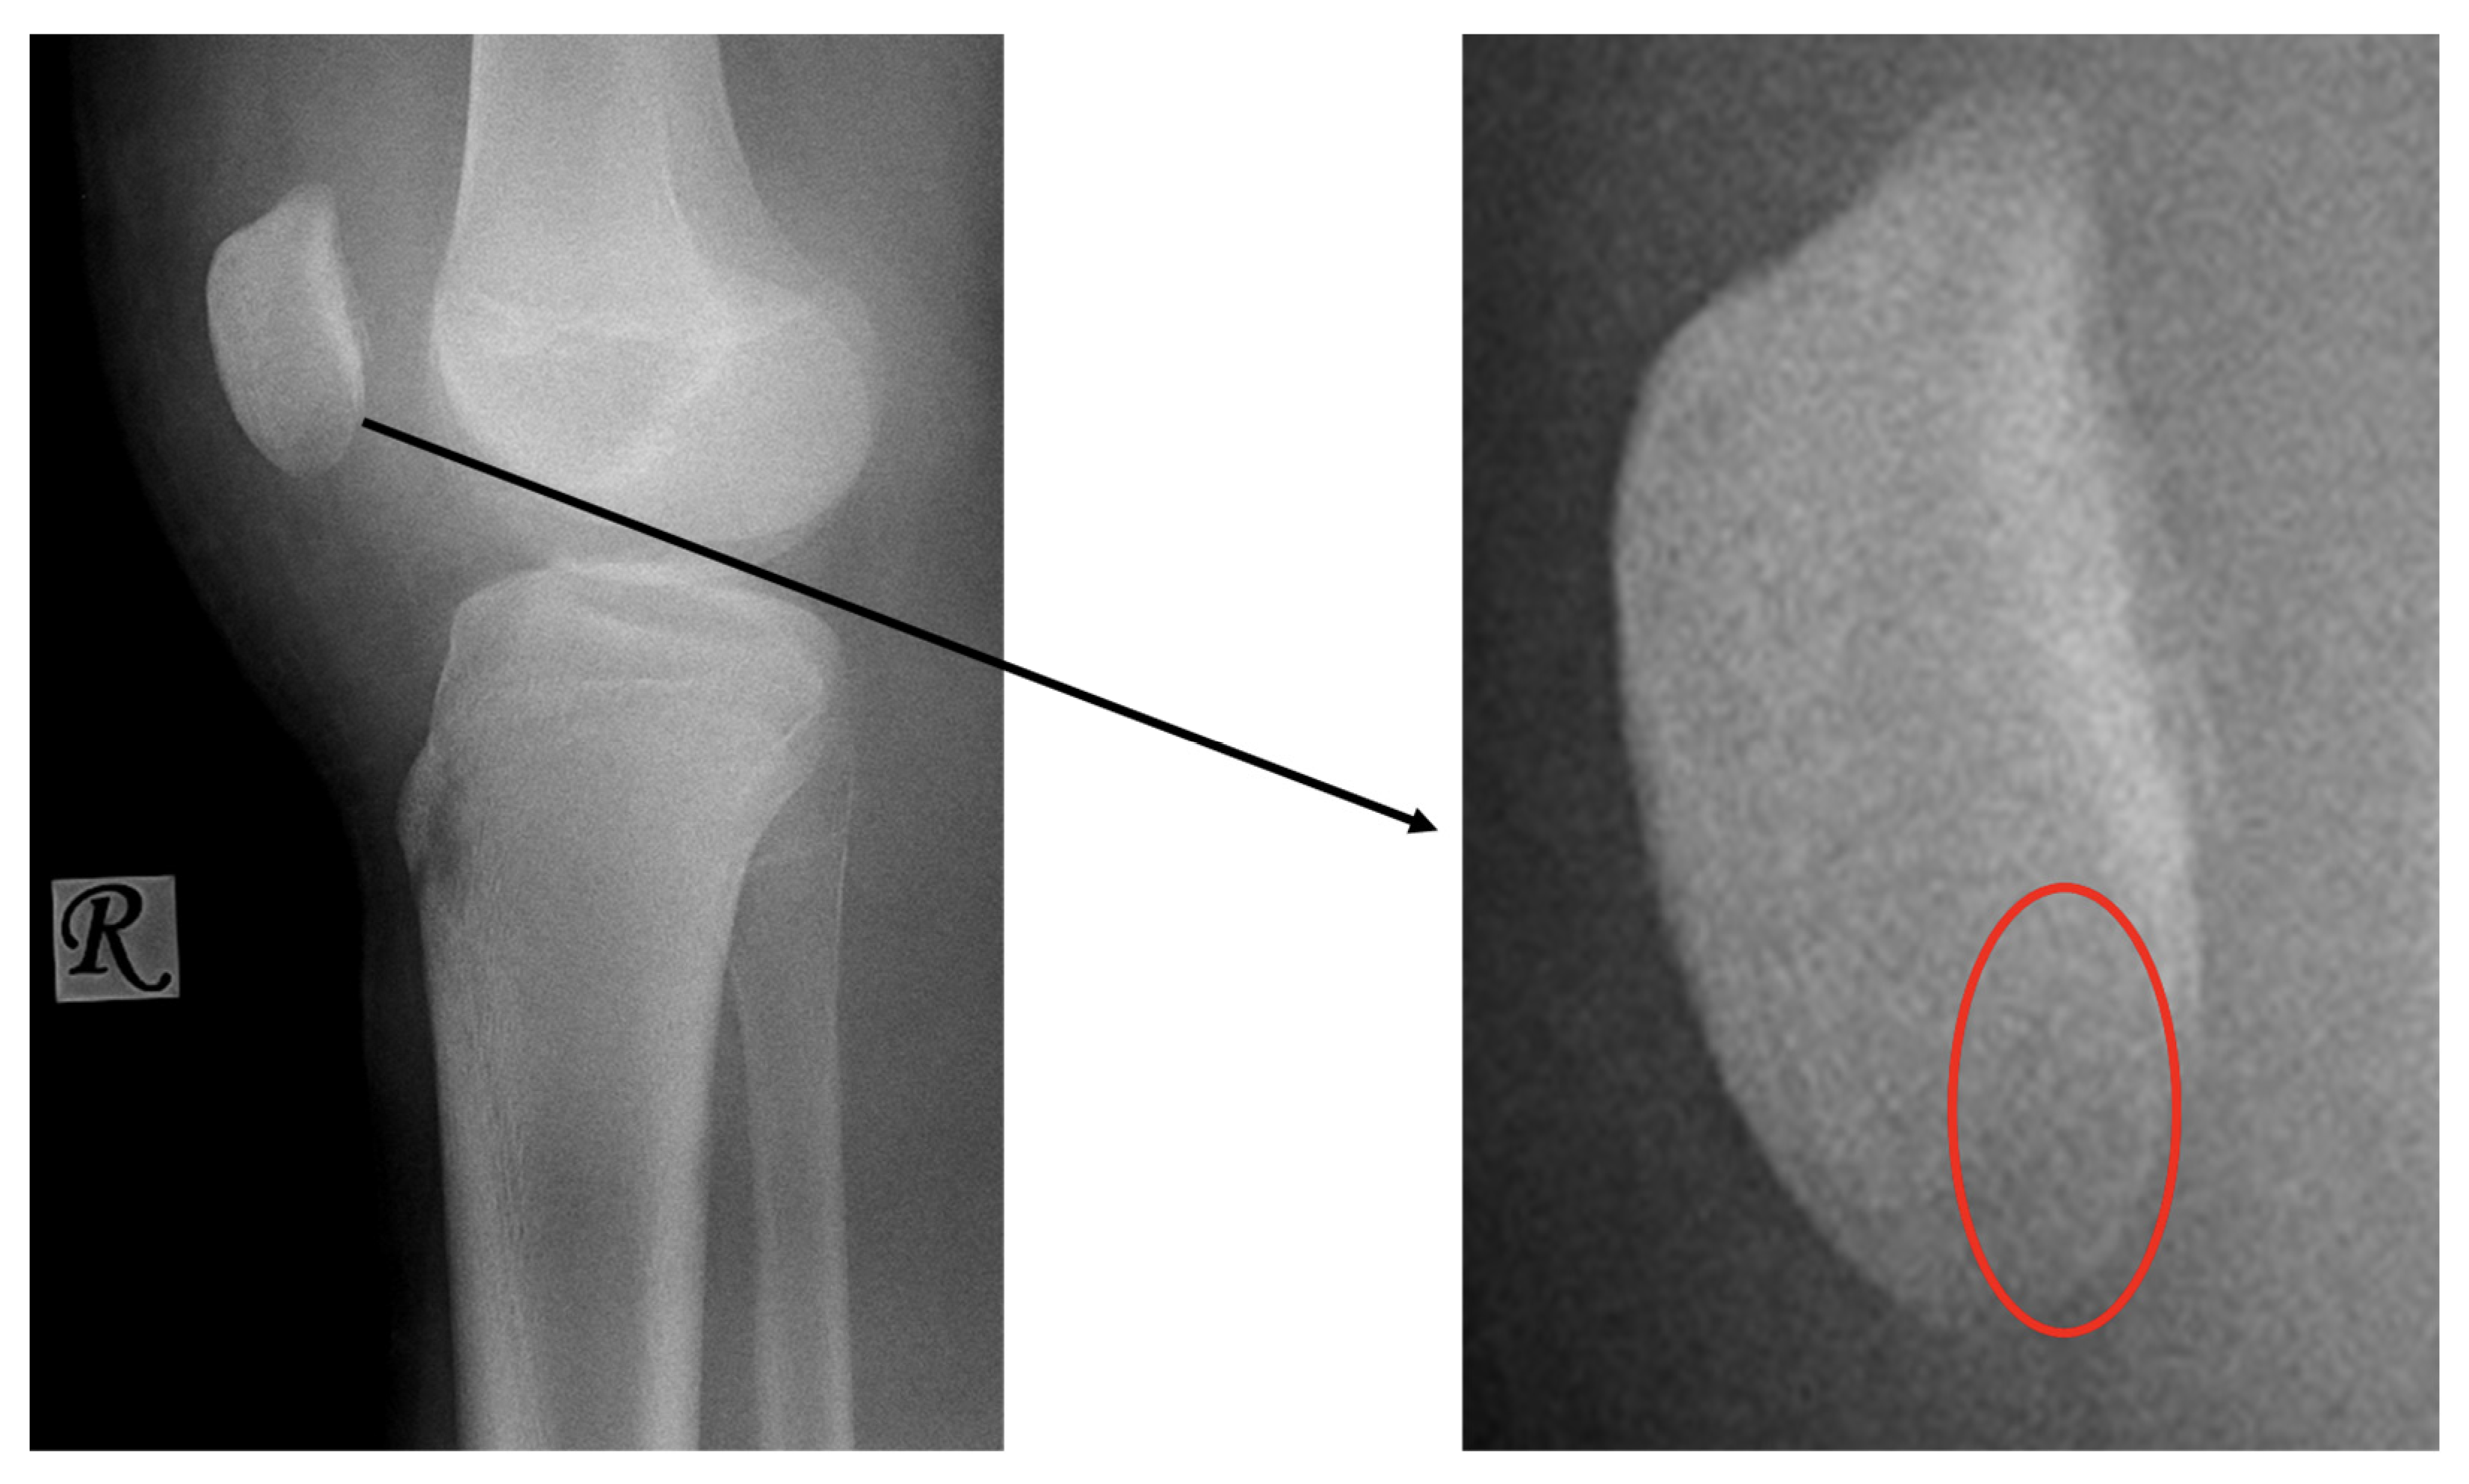

First patient: A nine-year-old girl injured her knee during a careless step, resulting in a sprain. The left knee was slightly swollen and the patient complained about pain, but other pathologies could not be identified with the physical examination. Therefore, an X-ray was requested. Results revealed an approximately 8 mm large broken piece of the femur’s lateral condyle, positioned at the border of the lateral recess (Figure 1).

Figure 1.

Preoperative X-ray showing the osteochondral fragment (yellow circle) of the lateral condyle of the femur.